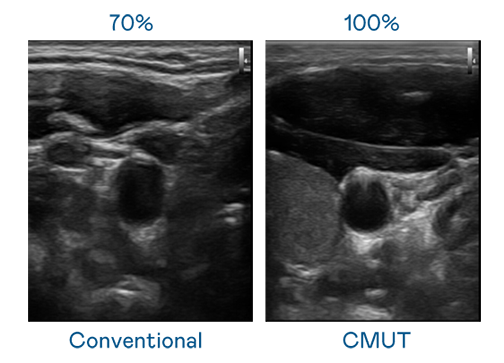

CMUT 技术是一种用电容式微机电元件来产生超音波讯号的技术。与传统 PZT 压电式技术相比,CMUT 频宽增加 30%,更宽频的超音波讯号让影像解析度大幅提升,是实现高影像品质医疗超音波扫描、促进精准医疗发展的关键技术。

超音波影像的解析度高低,首先取决于探头能发出的讯号频宽。尊龙 CMUT 可提供高清晰的超音波讯号,提供高频宽、高灵敏度、影像纹理细节更高的超音波影像,协助医护人员缩短影像判读时间及利用精准的医疗影像进行诊断。